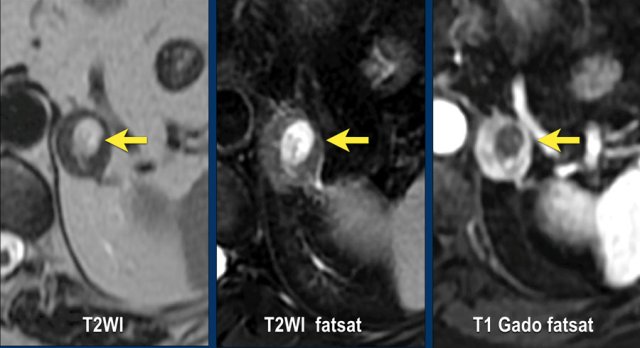

These images are of a 65- year-old female patient with an incidental discovery of a right adrenal mass on an abdominal ultrasound performed for renal stones.

The presence of microscopic fat is demonstrated by the signal drop on the opposed-phase image.

The patient was followed for 2 years, because the lesion is slightly inhomogeneous and measures 5.2 cm.

The lesion did not change in size and was not hormonally active.

It was diagnosed as a lipid-poor adenoma.

MRI performed for a left adrenal incidentaloma discovered on a non-contrast and arterial phase CT scan in a 61-year old male patient with an abdominal aneurysm.

On the non-contrast CT density was 18 HU.

T1 out-of phase image shows subtle inhomogeneous signal drop compared to in-phase.

Note that the fat-suppressed T1 does not help in the detection of microscopic intracellular fat.

Continue with next images.

The subtle central hyperintensity on the T1 fat sat is also hyperintense on the T2-weighted images and doesn't enhance on the post-contrast image.

After comparison with prior CT images from years before, the lesion turned out to be a slowly growing adenoma with recent internal hemorrhage.